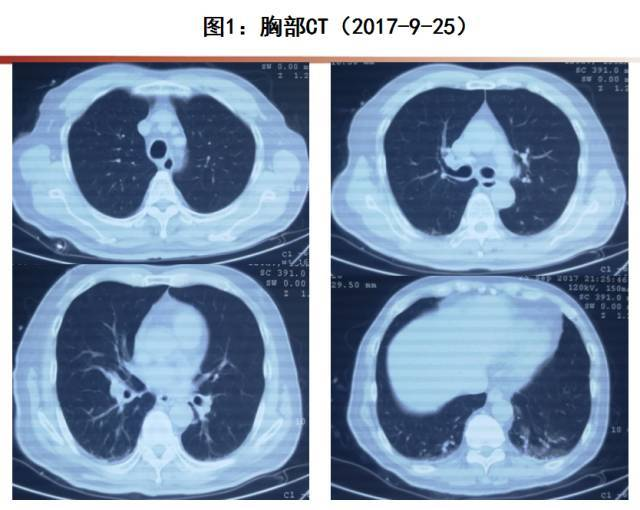

◉甲型H3N2流感病毒感染合并坏死性肺炎一例

这种情况在临床上被称为急性肺损伤(ALI)或急性呼吸窘迫综合征(ARDS)。数据显示,在重症流感患者中,约30%会发展为ARDS,而一旦进入ARDS阶段,死亡率可能高达40%-60%(数据来源:WHO)。